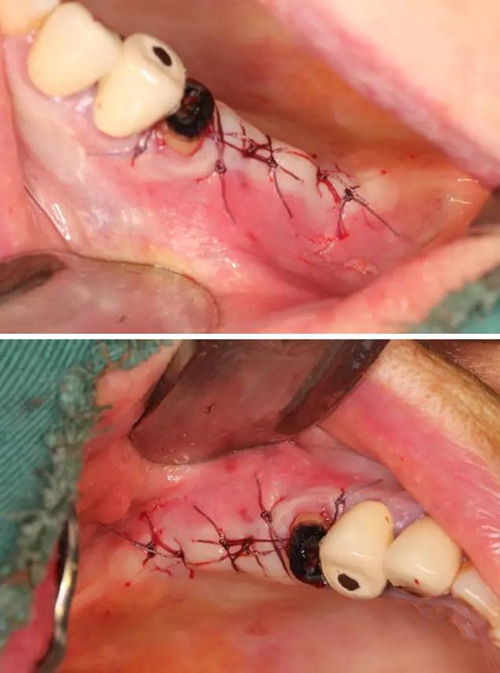

【病例分享】右上內(nèi)提+5冠延長1 梁光強